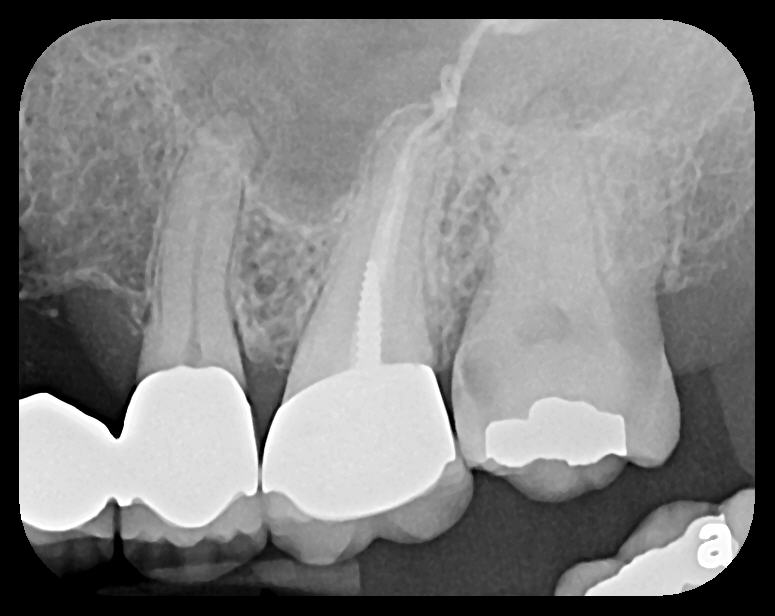

Fig 10.

A hemostat was used to obtain this PSP PA image of a potential fixed

prosthesis abutment, tooth No. 32. The hemostat is visible in the upper

left corner of the image. Hemostat stabilization of an HW sensor is

not possible and can damage the sensor if attempted.

Figure 10